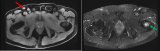

王晓慧:18F-FDG PET/CT显像甲状舌管囊肿伴鳞状细胞癌

18F-FDG PET/CT可以用于评估甲状舌管囊肿是否伴有鳞状细胞癌。据我们所知,没有人报道过术前18F-FDG PET/CT显像发现甲状舌管囊肿伴鳞状细胞癌。我们建议对于已确诊的甲状舌管囊肿伴鳞状细胞癌患者,可以使用18F-FDG PET/CT显像辅助评估其病变累及范围。 2022-06-26 PET/CT核医学